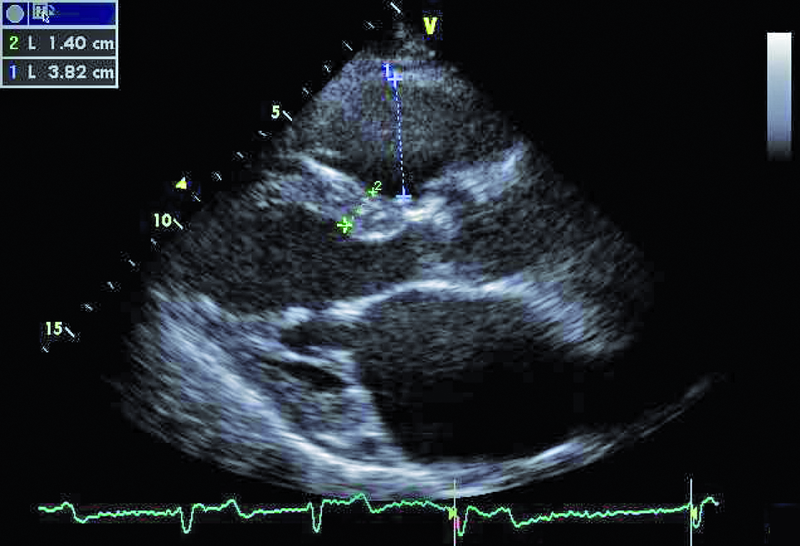

Kobieta, lat 80. Jakie patologie można rozpoznać na rycinach?

1. Powiększenie jamy prawej komory (ryc. 1).

2. Przerost mięśnia lewej komory (ryc. 1).